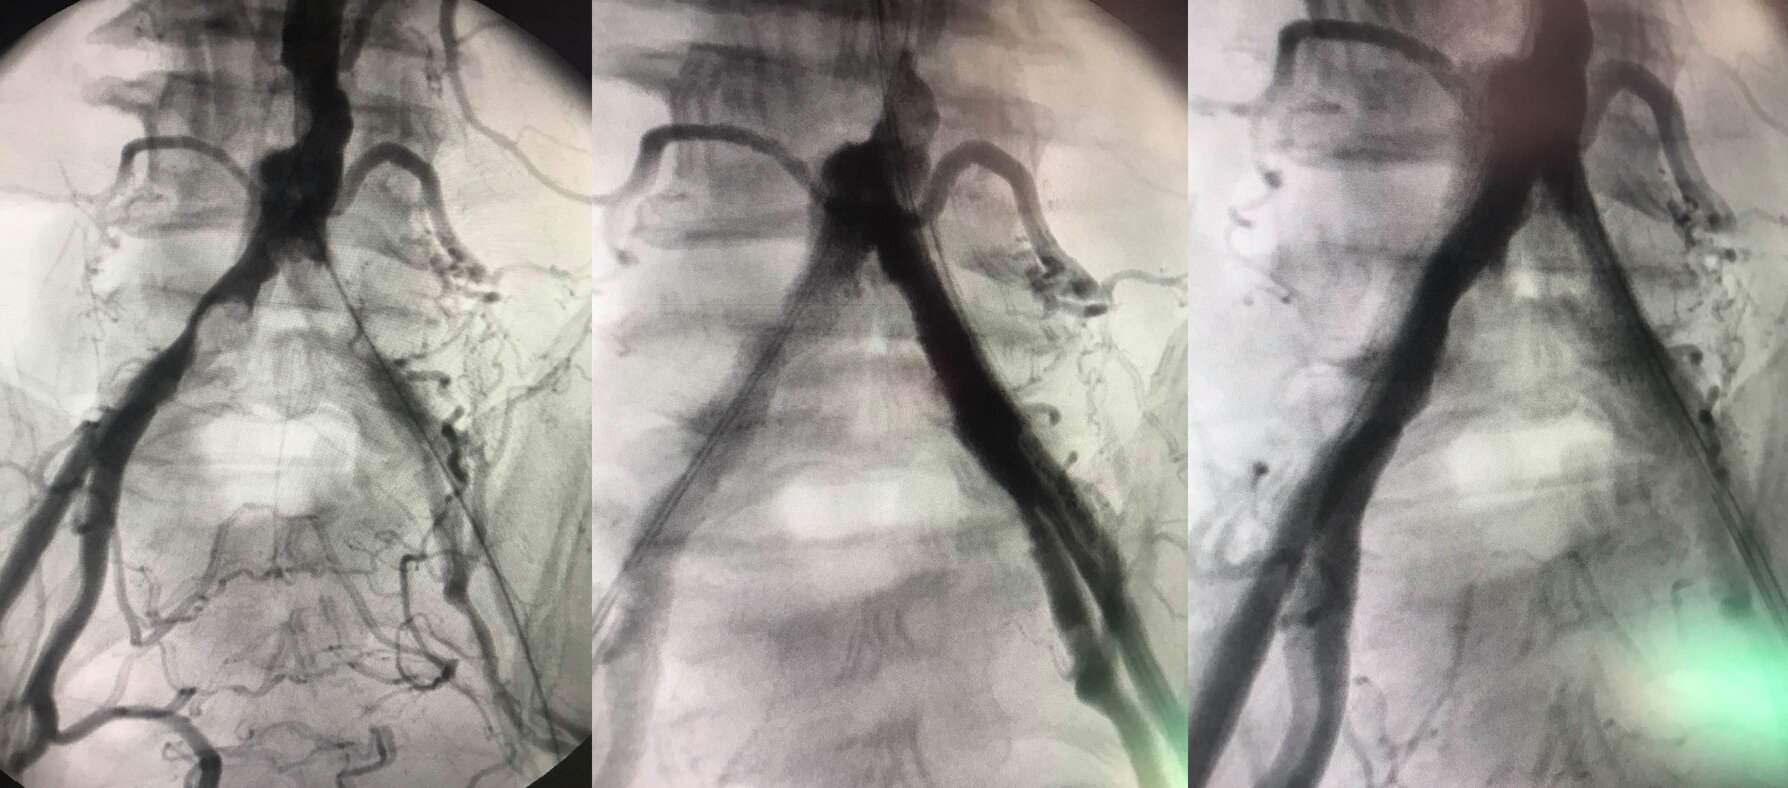

Ψηφιακή Αγγειογραφία και Ενδαγγειακές / Υβριδικές Τεχνικές,

Αγγειοπλαστική με Αεροθάλαμο και Τοποθέτηση Ενδοναρθήκων,

Κλασσική Ενδαρτηρεκτομή και Bypass Κάτω Άκρων

Ψηφιακή Αγγειογραφία και Ενδαγγειακές τεχνικές

Αορτική Ανευρυσματική Νόσος

Ενδαγγειακές Τεχνικές Αποκλεισμού, Κλασσική Ανοικτή Αποκατάσταση